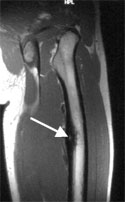

The RF ablation is performed under sterile conditions in the CT suite to optimally localize the lesion. A thin biopsy needle, canula and drill needle are used to access the osteoid osteoma.

A thin drill is placed in the osteoid osteoma nidus (arrow).